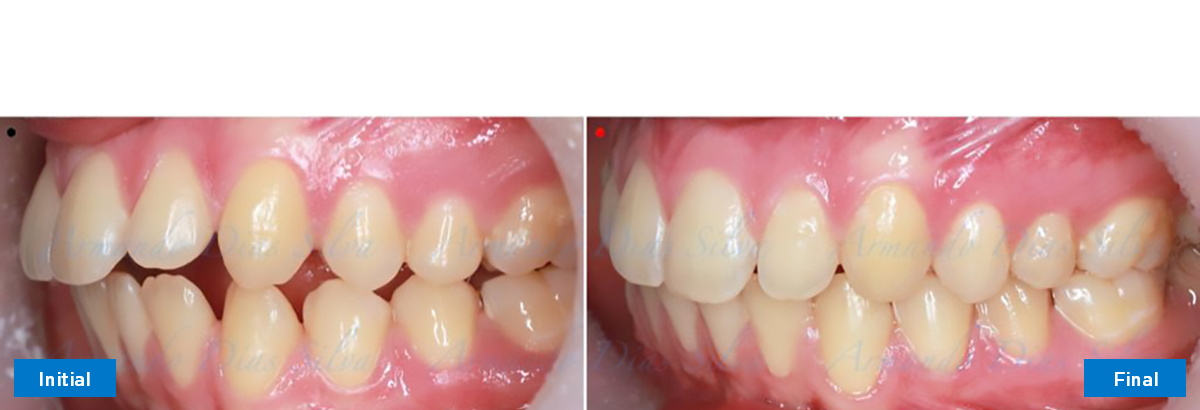

Clase II, Div. 1: Protrusión del incisivo central y espacios anteriores (SureSmile® Aligners)

Principal queja del paciente: Protrusión del incisivo central y mordida abierta. El paciente rechaza la expansión del arco palatino (MARPE) y las extracciones.

Este paciente adolescente presenta molares de Clase II y no le gusta su mordida abierta ni lo protrusivos que son sus dientes frontales. Por sus fotografías faciales, parece que su mandíbula es retrognática o le falta volumen en la barbilla. El historial del paciente también indica que existe un problema funcional al no haber guía de los incisivos.

• Molares de clase II

• El primer molar superior derecho está en una posición más mesial que el primer molar superior izquierdo

• Incisivos superiores e inferiores proclinados

• Orientación canina desfavorable

• Molares de clase I logrados con distalización y sin elásticos

• Sin expansión maxilar, respetando la envoltura periodontal

• Incisivos inferiores retroinclinados, que mejoran la estabilidad a largo plazo